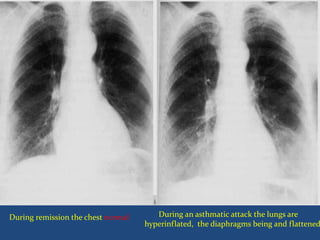

Normal chest X-ray during remissions.

 During attack the chest X-ray may show:

Signs of hyperinflation with depression of the

diaphragm and expansion of the retrosternal air space.

During an asthmatic attack the lungs are

hyperinflated, the diaphragms being and flattened

During remission the chest normal